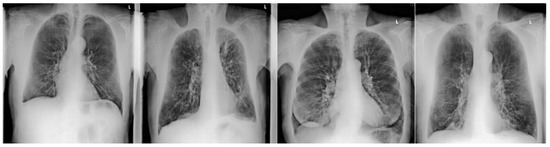

2. Materials and Methods

2.2. Data Acquisition

2.2.1. CR and DE Images

2.3.1. CR/DE Image Analysis